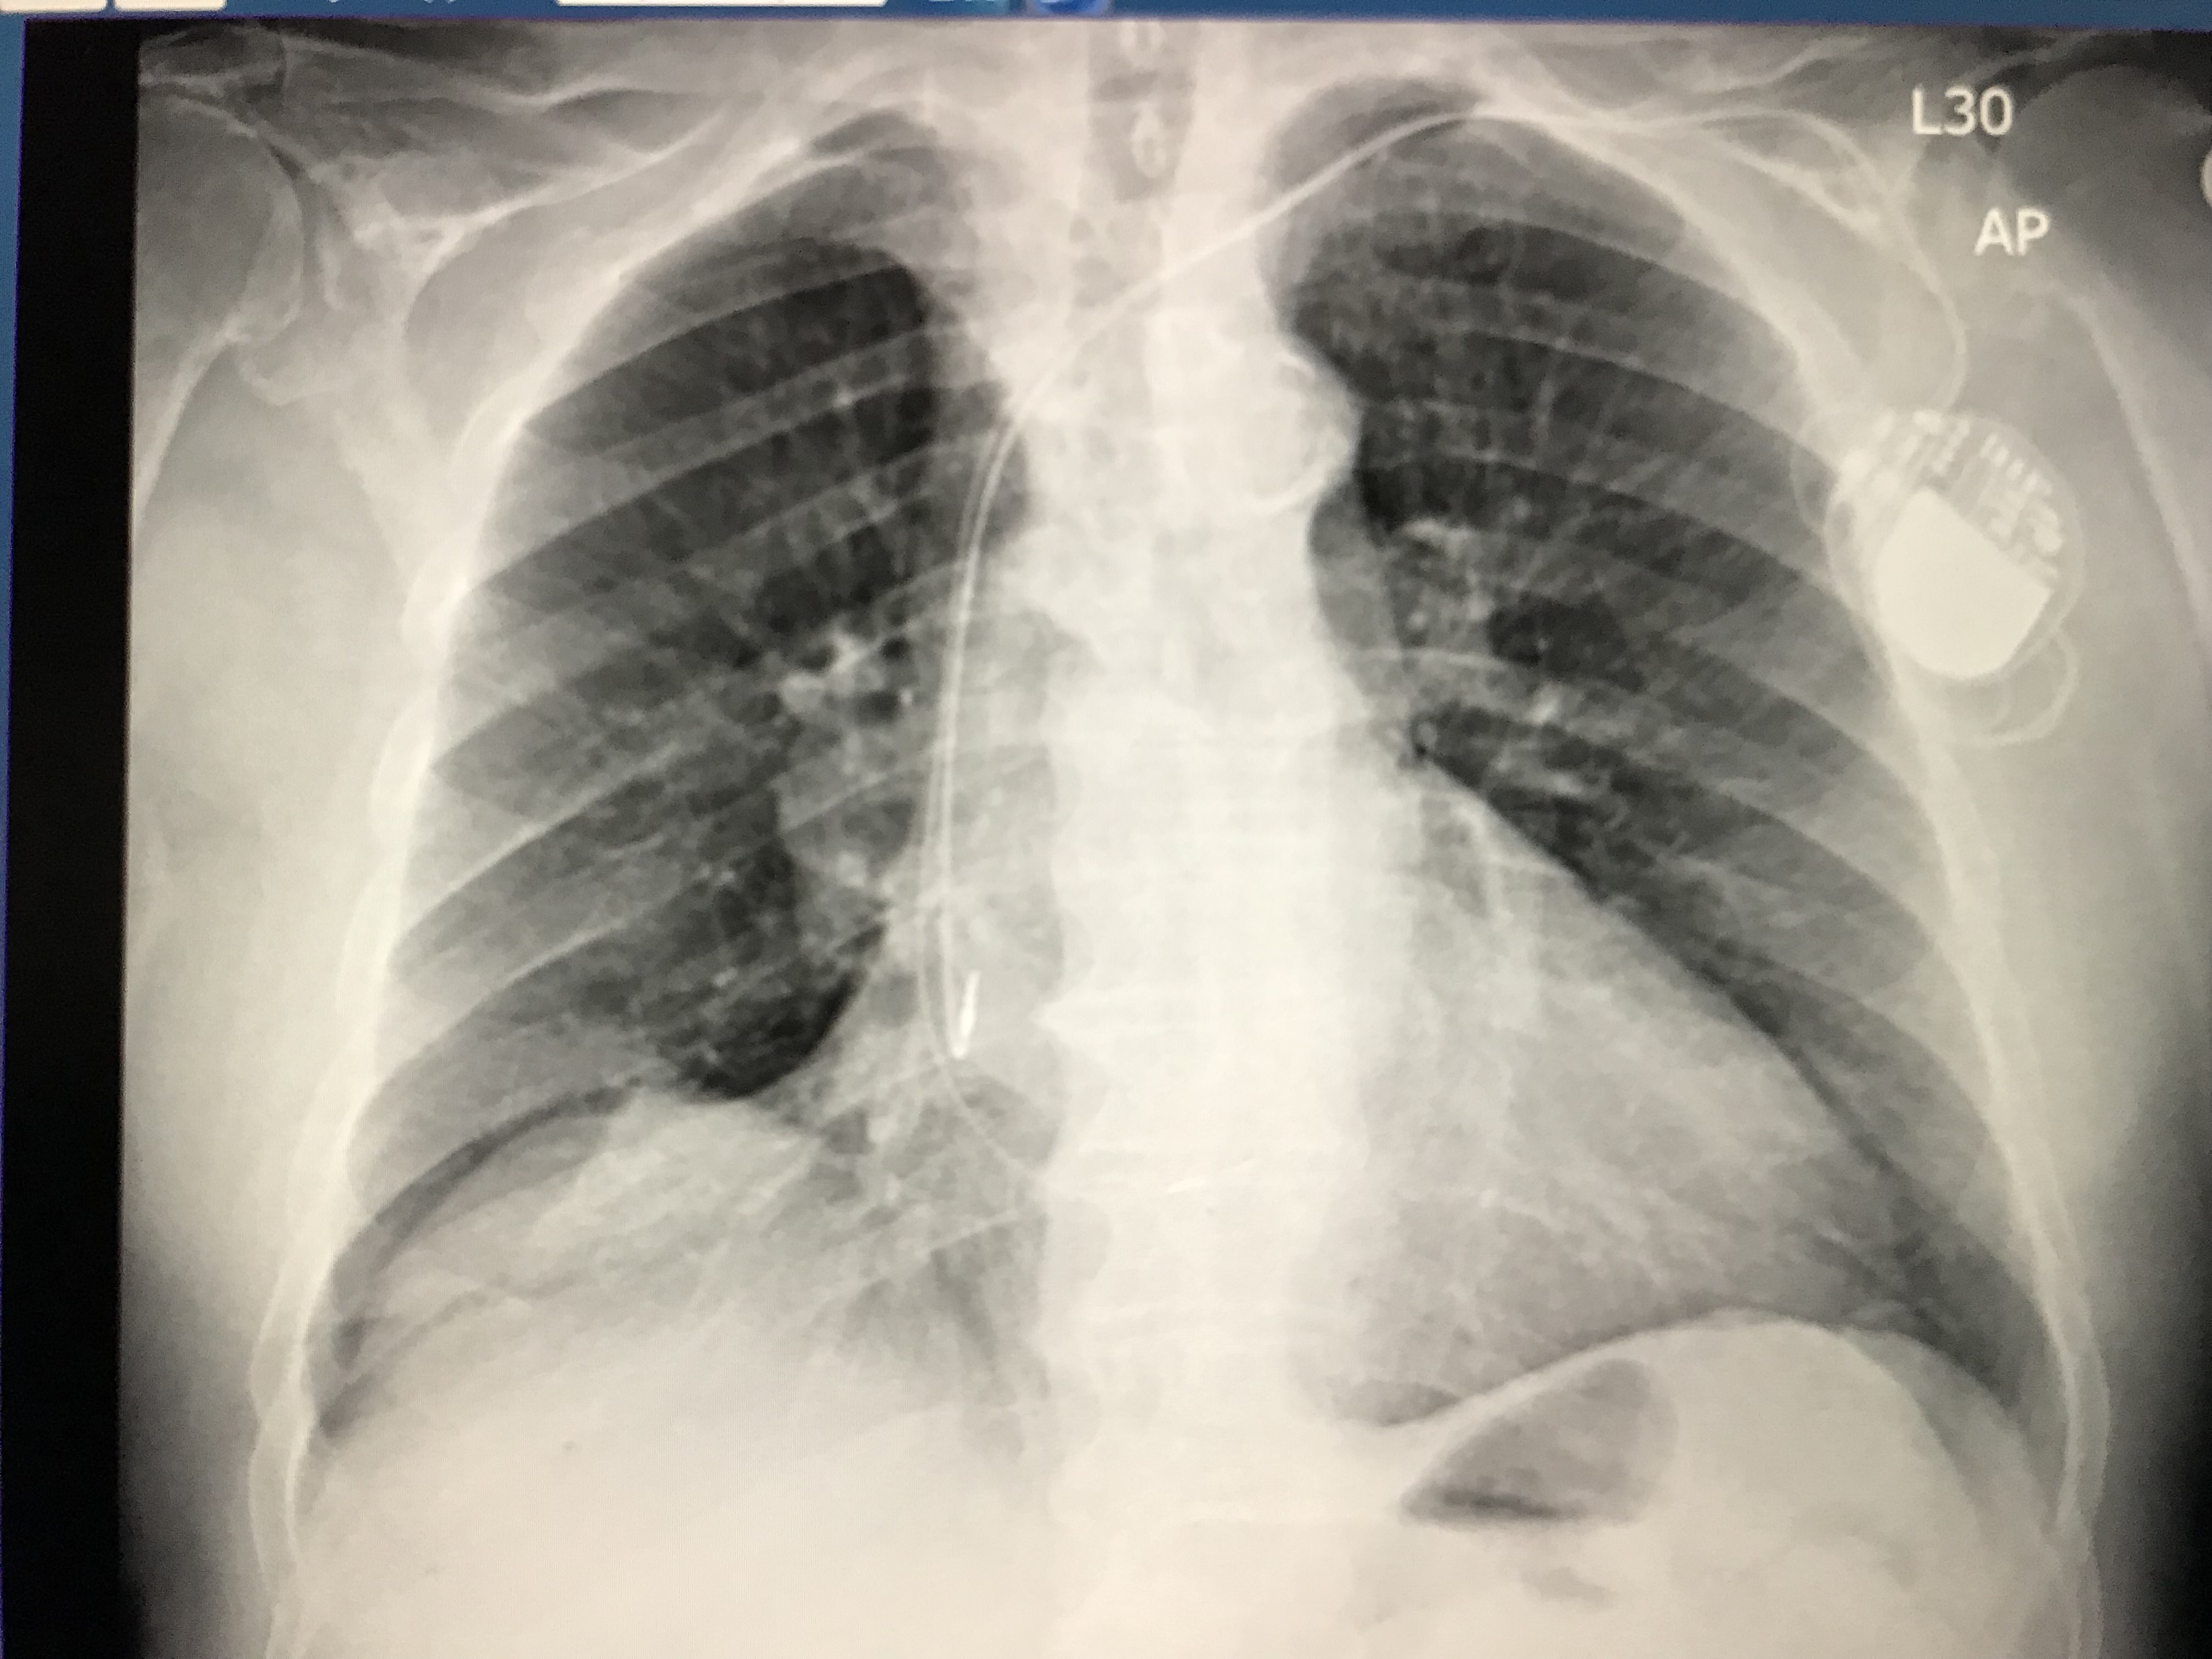

Kaszubskie Centrum Chorób Serca i Naczyń w Szpitalu Specjalistycznym w Wejherowie rozwija swoją działalność. 12 grudnia w Pracowni Elektroterapii i Elektrofizjologii Serca Oddziału Kardiologii i Angiologii Interwencyjnej w Wejherowie po raz pierwszy wszczepiono pacjentowi stymulator dwujamowy z elektrodą prawokomorową implantowaną bezpośrednio w pęczek Hisa.

Podczas zabiegu klasycznego, prawokomorową elektrodę stymulatora serca implantuje się w przegrodę międzykomorową lub w koniuszek prawej komory. Zawsze prowadzi to do zaburzeń synchronii skurczu komór serca, a często do różnego stopnia pogorszenia tolerancji wysiłku. Stymulacja pęczka Hisa jest najdoskonalszą metodą stymulacji, bo nie burzy synchronii skurczu komór i praktycznie przywraca fizjologiczną sekwencję stymulacji serca.

Zabieg przeprowadzili kardiolodzy z wejherowskiego szpitala: dr Roman Moroz i dr Adam Priebe przy wsparciu pielęgniarek Urszuli Cymanowskiej i Janiny Turskiej.